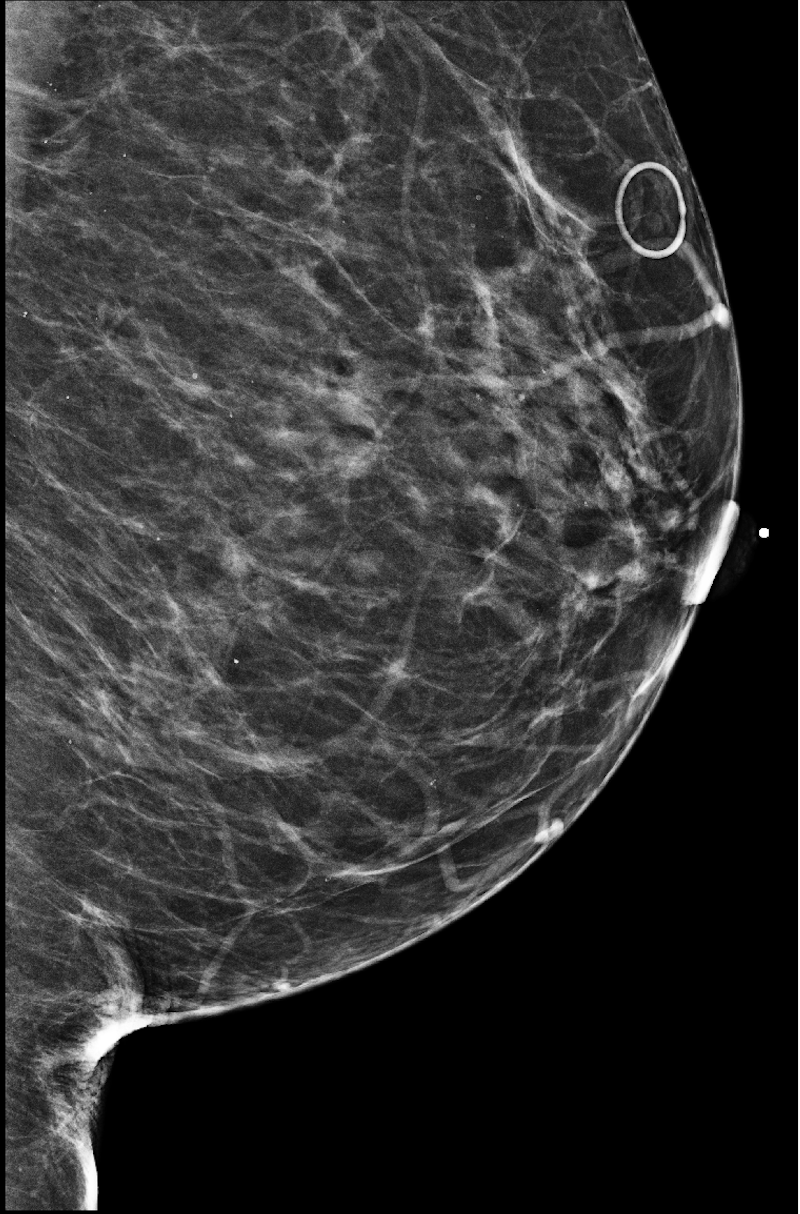

|

![]() |

| R-CC | L-CC |

| R-MLO | L-MLO |

The NYU Breast Cancer Screening Dataset [78] includes 229,426 exams (1,001,093 images) from 141,472 patients.222Our retrospective study was approved by our institutional review board and was compliant with the Health Insurance Portability and Accountability Act. Informed consent was waived. Each exam contains at least four images which correspond to the four standard views used in screening mammography: R-CC (right craniocaudal), L-CC (left craniocaudal), R-MLO (right mediolateral oblique) and L-MLO (left mediolateral oblique). An example is shown in Figure 3.

Across the entire dataset (458,852 breasts), malignant findings were present in 985 breasts () and benign findings in 5,556 breasts (). All findings are confirmed by at least one biopsy performed within 120 days of the screening mammogram. For the remaining screening exams that were not matched with a biopsy, we assigned labels corresponding to the absence of malignant and benign findings in both breasts. In each exam, the two views of the same breast share the same label.

For all exams matched with biopsies, we asked a group of radiologists (provided with the corresponding pathology reports) to retrospectively indicate the location of the biopsied lesions. This way we obtained the segmentation labels: where if pixel belongs to the benign/malignant findings. An example of such a segmentation is shown in Figure 3. In all experiments (except for experiments in Section 3.6 that assess the benefits of utilizing segmentation labels), segmentation labels are only used for evaluation. We found that, according to the radiologists, approximately of exams were mammographically occult, i.e., the lesions that were biopsied were not visible on mammography, even retrospectively, and were identified using other imaging modalities: ultrasound or MRI.